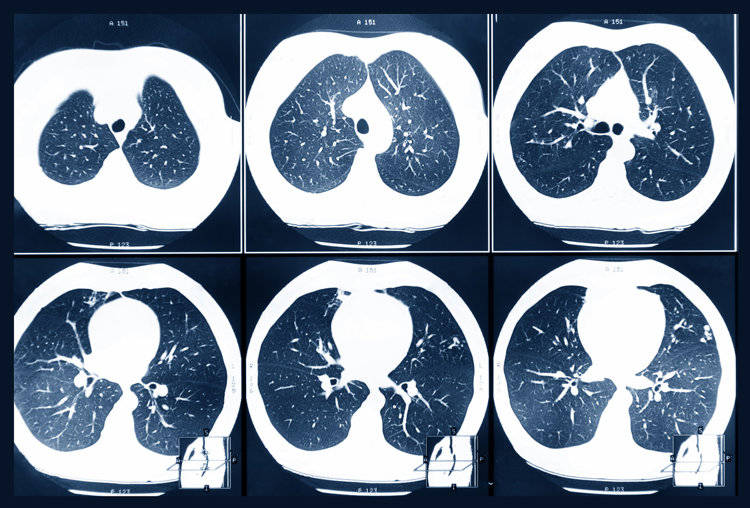

很多人看到 “肺结节” 三个字就慌了神,其实肺结节只是影像学上的一个描述术语,指的是在胸片或 CT 上观察到的、直径小于 3 厘米的圆形或类圆形肺部阴影。根据直径大小,它还分为肺小结节(直径 1-3 厘米)和微小结节(直径小于 1 厘米)。从临床数据来看,80%-90% 的肺结节都是良性的,可能是肺炎愈合后留下的瘢痕、肺结核病灶、肺部淋巴结,或是炎症引起的增生组织。即便少数肺结节被确诊为肺癌,也大多处于早期阶段,此时肿瘤体积小、未发生转移,通过手术切除等治疗手段,5 年生存率能达到 90% 以上,预后效果良好。

首先是结节密度增加。肺结节按密度可分为实性结节、纯磨玻璃结节和混合型磨玻璃结节。其中,混合型磨玻璃结节的癌变风险最高 —— 它既包含磨玻璃样的模糊区域,又有能遮盖后方肺组织和血管的实性成分,临床数据显示其癌变几率超过 60%。如果体检后复查时发现结节密度逐渐升高,尤其是出现实性成分,一定要立即就医,进一步检查明确性质。

其次是结节体积变大。结节的大小与恶性概率密切相关,直径越小,良性可能性越高;直径越大,恶性风险越大。一般来说,直径小于 5 毫米的微小结节,恶性概率不足 1%;但当直径超过 8 毫米时,癌变率会显著增加。如果在短期内(比如 3-6 个月)复查发现结节明显增大,或直径快速接近甚至超过 1 厘米,需要及时联系呼吸科或胸外科医生,评估是否需要手术切除或穿刺活检。

此外,体检报告中若出现 “血管集束征”“胸膜牵拉征”“边缘不规则”“毛刺征”“分叶征” 等描述,也需要高度警惕。这些特征往往提示结节可能存在恶性倾向 —— 比如 “毛刺征” 指结节边缘不光滑,像有细小的 “毛刺” 向外延伸;“分叶征” 则是结节边缘呈现凹凸不平的 “分叶状”,这些都是肺癌早期的典型影像学表现。一旦出现这些描述,应尽快到专科门诊就诊,通过增强 CT、PET-CT 或病理活检等检查,明确结节性质。